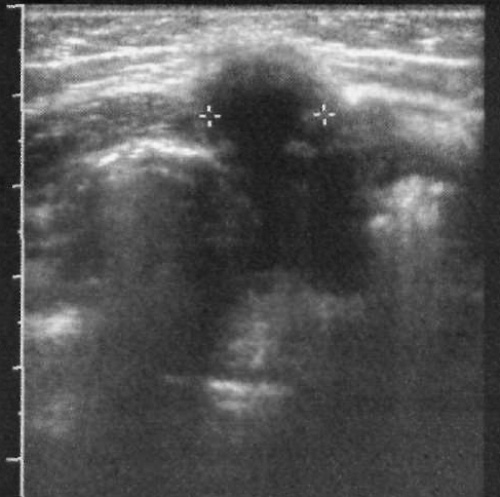

При открытом урахусе на УЗИ в сагиттальной плоскости наблюдается узкую полость, заполненную жидкостью. Эта полость находится между куполом мочевого пузыря и поверхностью пупка. Также могут обнаруживаться такие аномалии развития, как срединные кисты урахуса, локализованные между куполом пузыря и пупком (эти кисты могут быть анэхогенными, а в случае инфекции в них часто образуется осадок), пазуха урахуса (фото 8) и дивертикул урахуса, который визуализируется как заполненная жидкостью структура, прилегающая к куполу мочевого пузыря.

Фото 8. Пазуха урахуса. Поперечное ультразвуковое изображение околопупочной области у младенца. Курсорами обозначен канал, заполненный жидкостью, который приближается к куполу мочевого пузыря в продольной проекции (не показана), но несоединенный с ним. Исследование проводили с помощью линейного датчика